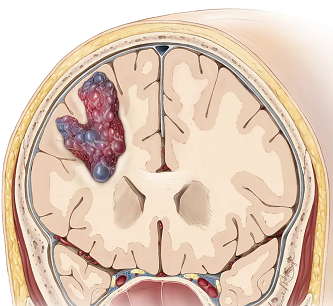

脑内可能也会生长“爆米花”,爆米花只是一个形象的比喻,“爆米花”其实是脑海绵状血管瘤的一个典型影像特征。爆米花可成蘑菇形和球形、不规则形态,基本形状是球形。

海绵状血管瘤,又称海绵状血管畸形,是由众多薄壁血管组成的海绵状异常血管团;其外观形似“爆米花”或“桑葚”,剖面呈海绵状或蜂窝状,直径介于2毫米至数厘米不等;显微镜下,海绵状血管瘤由扩张的薄壁毛细血管构成,血管壁中缺少弹力纤维和平滑肌。